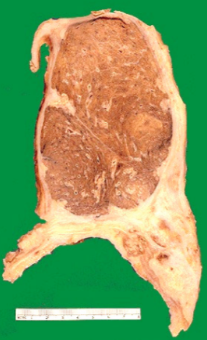

66yo male with heavy smoking history presents with new onset haemoptysis on a background of COPD. A mass is seen on CXR

Lung cancer